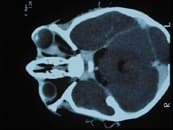

CT scan of a different person who has an orbital mass. Note the resulting proptosis of the left globe, another finding suggestive of an orbital mass. |